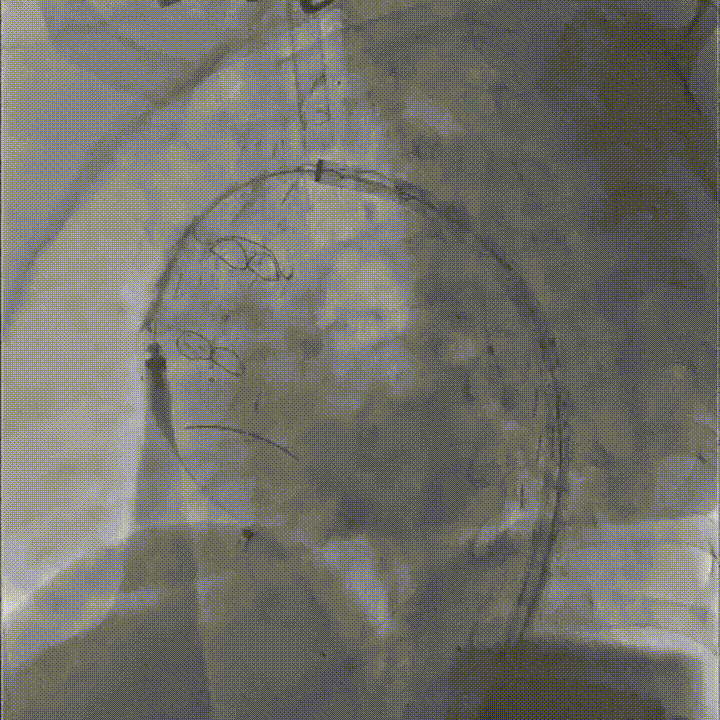

置入双分支术中支架

术后影像